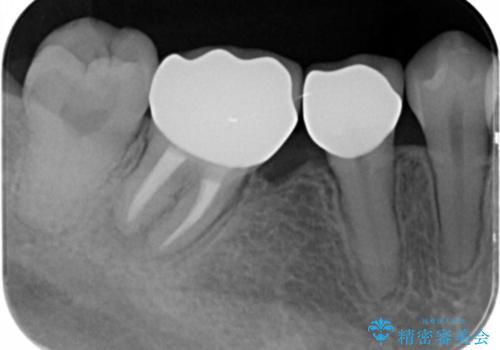

- 見栄えが悪く、歯ブラシのしづらい銀歯を白くしたい、とセラミック治療を希望され来院されました。

歯が傾いているため、歯間ブラシや歯ブラシのしやすさを考慮し、汚れの溜まりにくいようなクラウン設計を行います。